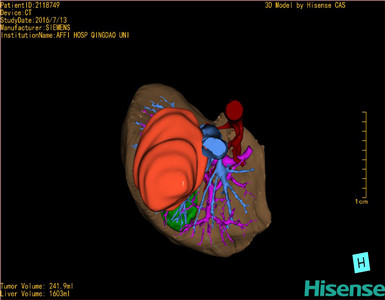

将0.625mm双源薄层CT资料的静脉期和动脉期Dicom格式文件导入海信CAS系统。

通过调节窗宽窗位调整CT序号,对肿瘤,肝实质,胆囊,下腔静脉,肿瘤,肝动脉、门静脉及肝静脉等进行三维重建;系统自动计算肿瘤体积和肝脏体积。

模拟手术操作,自动计算切除肿瘤体积。肝脏体积为1603ml,肿瘤体积为241.9ml,肿瘤体积为肝脏体积的15.1%,通过比对70-80岁正常肝脏体积为1118.08±190.14ml,通过术前模拟手术,精准判断切除后剩余肝脏体积能耐受,避免肝衰竭发生。

术前三维重建:

重建图片